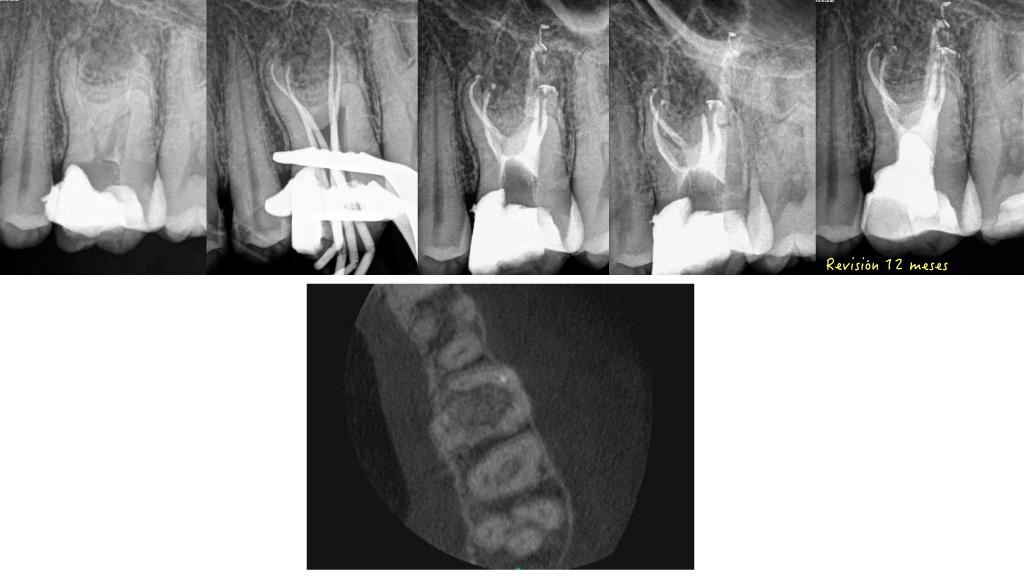

Empiezo una página Facebook nueva (https://www.facebook.com/endodonciabadajoz), con un caso , a mi gusto precioso, lo que para mi es la endodoncia actual , donde necesitamos tener tecnología y conocimientos sumados a un poco de «maña»…. Se trata de un 3.6 con una anatomía que hemos visto muchas veces y que pensamos y esperamos que nunca nos toque:

De este caso que os muestro, he aprendido varias cosas, primera y muy importante, es que el PODER DEL IRRIGANTE solo actuar en aquellas zonas donde la preparación mecánica le ha dejado entrar, por lo que la gran importancia de eliminar mecánicamente tejido o detritus para que el irrigante pueda hacer su trabajo no se debe olvidar.

Y segundo, y quizás más importante , y que muchas veces olvidamos, es que por vía ortógrada, el tratamiento de endodocia , EN OCASIONES, tiene un límite, para unos uno y para otros otro, pero ÉXISTE. Por lo que necesitamos COMPLEMENTAR el tratamiento por vía retrógrada para manejar el caso.

Cada vez somos más conscientes de la dificultad anatómica de los molares inferiores . Con la ayuda de las microtomógrafías dentales de compañeros en estudios in vitro, que nos hacen ver la complejidad de la raíz mesial, podemos darle la explicación y entender la necesidad el manejo del abordaje quirúrgico para tratar esas piezas.